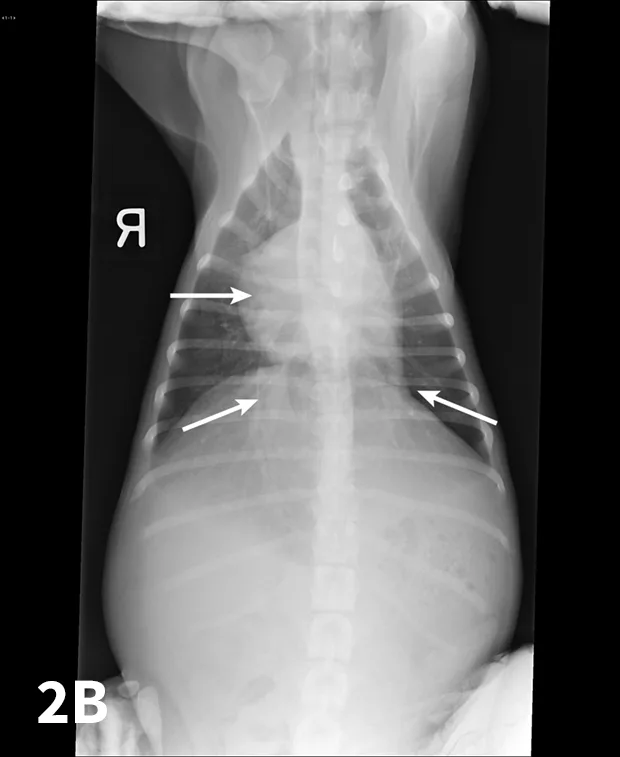

Abdominal ultrasonography is helpful to evaluate the patient for other underlying conditions and to evaluate the hepatic vessels (Figure 3).

Abdominal ultrasound image documenting enlarged hepatic vessels consistent with right-sided heart failure.